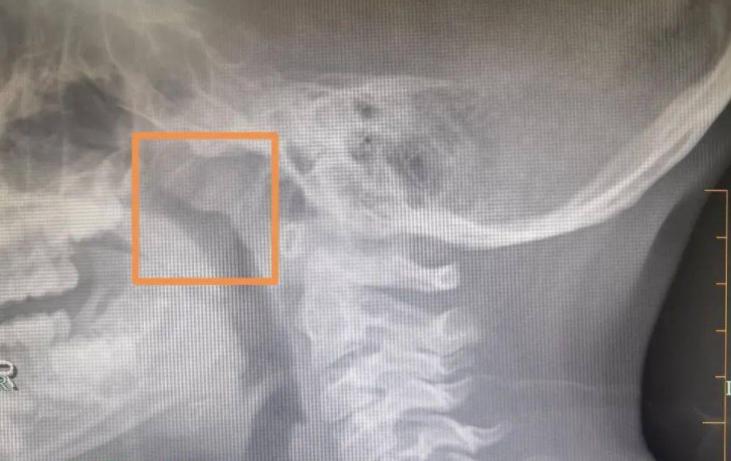

耳朵問題的「時間跨度」尤其關鍵。如果你發現自己耳鳴超過兩周,或者耳後腫塊超過一個月不消,即使沒有其他症狀,也該去檢查。不是去挖耳朵,而是做一個鼻咽、頸部的影像學檢查,可能更有意義。

從健康管理的角度,耳朵其實是一個很值得關注的「哨兵」。它靠近大腦,連接咽喉,通著氣道,周圍布滿神經和血管。這個結構複雜的區域,小小的風吹草動,可能牽出一連串的問題。